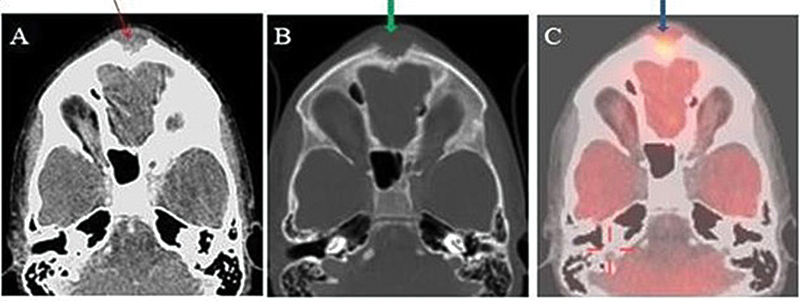

There was no pallor or organomegaly. Positron emission tomography-computed tomography was done outside our institute that revealed a hypermetabolic osteolytic lesion in the frontal bone in the midline as shown in [Fig. 1] and D10 vertebra body associated with soft tissue component. Pleural and parenchymal nodules with associated mediastinal lymph nodes (left hilar, left prevascular, aorta pulmonary, paratracheal, pretracheal and subcarinal nodes) were also seen as shown in [Fig. 2]. A frontal bone lesion biopsy was performed under ultrasonography guidance for further assessment, and the sample was tested for acid-fast bacilli staining and polymerase chain reaction (cartridge based nucleic-acid amplification) testing. Results revealed necrotizing granulomatous inflammation of TB etiology. The patient took antitubercular drugs including rifampicin (10 mg/kg), ethambutol (15 mg/kg), isoniazid (5 mg/kg), and pyrazinamide (25 mg/kg) for a period of 3 months followed by rifampicin (10 mg/kg) and isoniazid (5mg/kg) for the next 9 months. The swelling size reduced and complete resolution of the scalp lesion was noted 3 months post initiating the therapy.

| Figure 2: (A, B) Axial positron emission tomography-computed tomography (PET-CT) shows a lytic lesion with associated soft tissue involving body of D10 vertebrae. (C, D) Axial PET-CT shows pleura and parenchymal nodules with associated mediastinal lymph nodes with foci of calcification within.